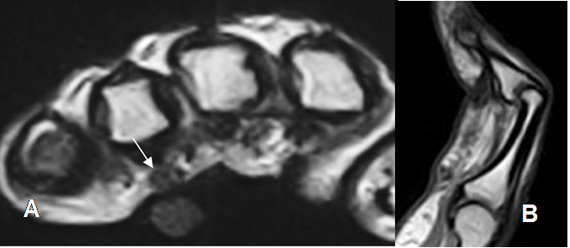

Fig 96 A. Enfermedad de Dupuytren.

A: RM axial en T2. Imagen hipointensa superficial, en la parte anterior del 4º metacarpiano, que Corresponde a tracto de fibrosis.

B: RM sagital en T1. Deformidad en flexión del dedo, por la fibrosis secundaria.